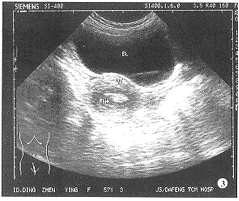

经直肠超声引导精囊穿刺注药治疗精囊炎